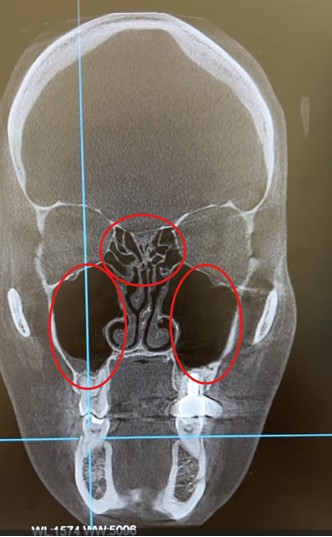

Через 10 дней после начала лечения (третий прием) пациентка активных жалоб не предъявляла. Контрольная КТ показала, что все пазухи полностью пневматизированы (свободны от патологического содержимого). В диагнозе было констатировано выздоровление после острого пансинусита и хронического полипозного риносинусита.

Видео: КТ после лечения